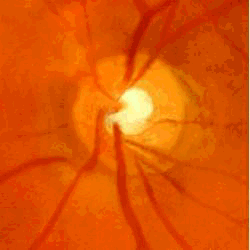

Pronostic pour un glaucome

En général, le glaucome évolue très lentement et les premiers symptômes apparaissent tardivement.

Le plus souvent, lorsqu’il est diagnostiqué tôt et bien traité, la maladie n’évolue plus et la vision se stabilise.

En l’absence de diagnostic et de traitement, il peut aboutir à la cécité complète et définitive.